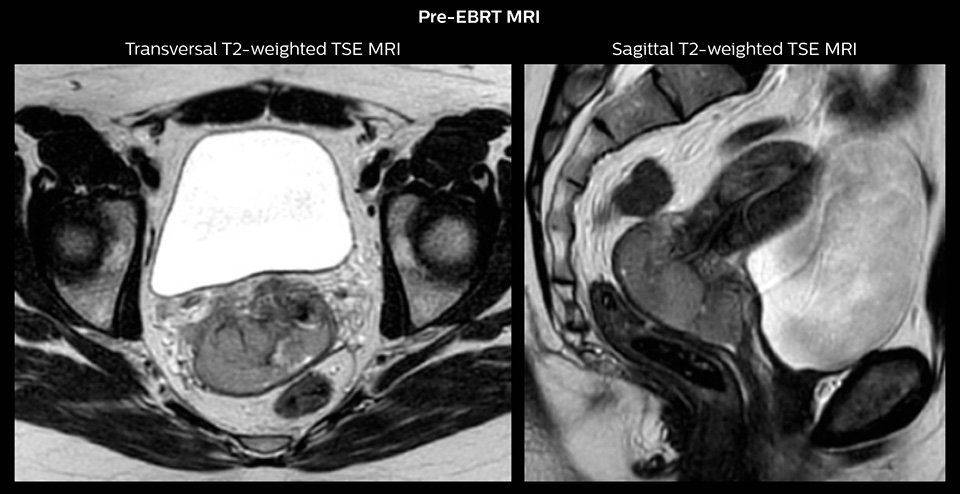

Case study: MR-guided brachytherapy in patient with cervix cancer

Patient history

Stage IIB cervix cancer patient with a primary tumor with width of 6.0 cm and proximal/distal infiltration of left/right parametria at diagnosis. The patient had one PET-positive external iliac lymph node.

The patient was treated with external beam radiotherapy (EBRT) and concomitant chemotherapy. EBRT was delivered as IMRT with daily IGRT and a total dose of 45 Gy in 25 fractions to the pelvis and 55/25 fractions to the PET-positive lymph node. There was good tumor response during therapy and towards the end of EBRT the primary tumor had regressed to 3.8 cm width and proximal parametrial infiltration.